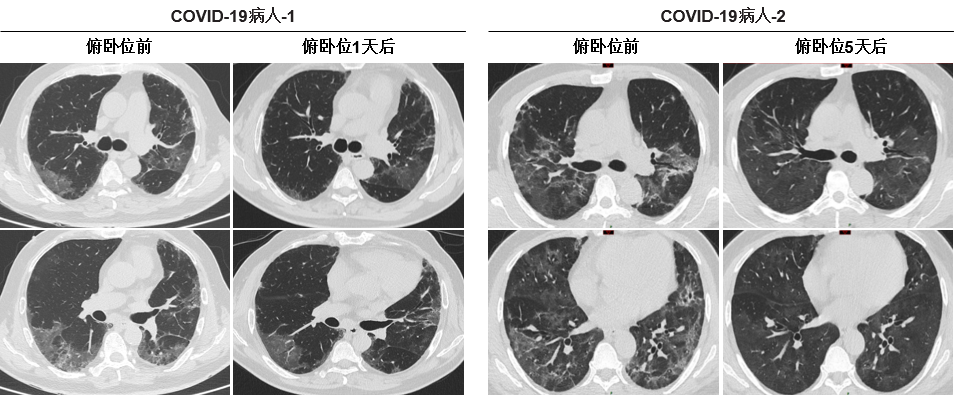

随着COVID-19的全球流行,截至2020年8月6日,共有19,093,957人感染,死亡713,408人,死亡率为3.7%。许多COVID-19患者因严重缺氧而死亡,找到一种简单有效的COVID-19患者治疗方法显得尤为重要。从2020年2月1日至2020年4月30日,共有60名COVID-19严重缺氧患者入组。23例患者采取早期俯卧位,37例患者未采取。在俯卧位组,30分钟后脉搏血氧饱和度(SpO2)从91.09±1.54%增加到95.48±1.73%(P <0.01)。呼吸频率(RR)从28.22±3.06次/分钟降至24.87±1.84次/分钟(P <0.01)。ROX指数从3.35±0.46增加到3.96±0.45(P <0.01)。然而,非俯卧位组的SpO2、RR和ROX指数没有显著差异。此外,早期俯卧位也可明显改善一些患者的CT成像表现。随访90天后,俯卧位组有10例(43.5%)COVID-19患者死亡,而非俯卧位组有28例(75.7%)COVID-19患者死亡。对于早期俯卧位改善缺氧的潜在机制,推测可能是由于血流重新分布引起的,水肿液在重力作用下重新分布到腹侧,萎缩性肺泡在俯卧位时重新开放,导致V/Q改进。总之,这项工作将有助于临床医生利用俯卧位治疗严重缺氧的COVID-19患者,降低严重缺氧的COVID-19患者的死亡率,对于COVID-19患者的治疗有一定的指导意义。